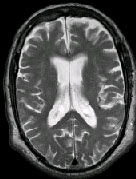

IMAGING FINDINGS: The CT was performed on AIC’s new 16-slice helical multi-slice CT (MSCT). Both routine single-slice and thin-section helical scans were obtained and 3D/Multiplanar images were performed on the Advanced 3D workstation. Fig. 1 shows an image at the level of the lateral ventricles with possible high density within the sulci on the right (arrow). To confirm this finding, an MRI with contrast was then obtained on AIC’s 1.5-Tesla high-field, short-bore Siemens MRI. Fig. 2a-b are T2-weighted images at the same level showing NO definite abnormality. T1-weighted images (not shown) were also negative. The post-contrast images (not shown) showed NO abnormal enhancement in this region, either. Diffusion-weighted images were also negative. However, Fig. 3a-b, which are FLAIR images, demonstrate clear hyperintensity within multiple sulci involving the right temporo-parietal area (arrows).

DIAGNOSIS: The FLAIR images are compatible with Subarachnoid disease. The Differential Diagnosis includes: (1) Subarachnoid Hemorrhage (SAH); (2) Meningitis; (3) Infarct; (4) Flow Artifact. Lack of enhancement is against meningitis. Acute infarct was ruled out on the basis of negative Diffusion MRI and lack of cytotoxic edema on the FLAIR images. Focal abnormality is against flow artifact (which is more diffuse and usually in the posterior fossa on FLAIR images). The clinical history of trauma and the high-density on CT and hyperintensity on FLAIR images within the sulci are diagnostic of Acute Post-traumatic Subarachnoid Hemorrhage (SAH).

DISCUSSION: MRI FLAIR imaging is the modality of choice for diagnosis of supratentorial SAH. In the posterior fossa, however, CT is superior due to flow artifacts on FLAIR images in the peripontine/ambient cisterns. A combination of CT and MRI would be ideal to optimize detection sensitivity.